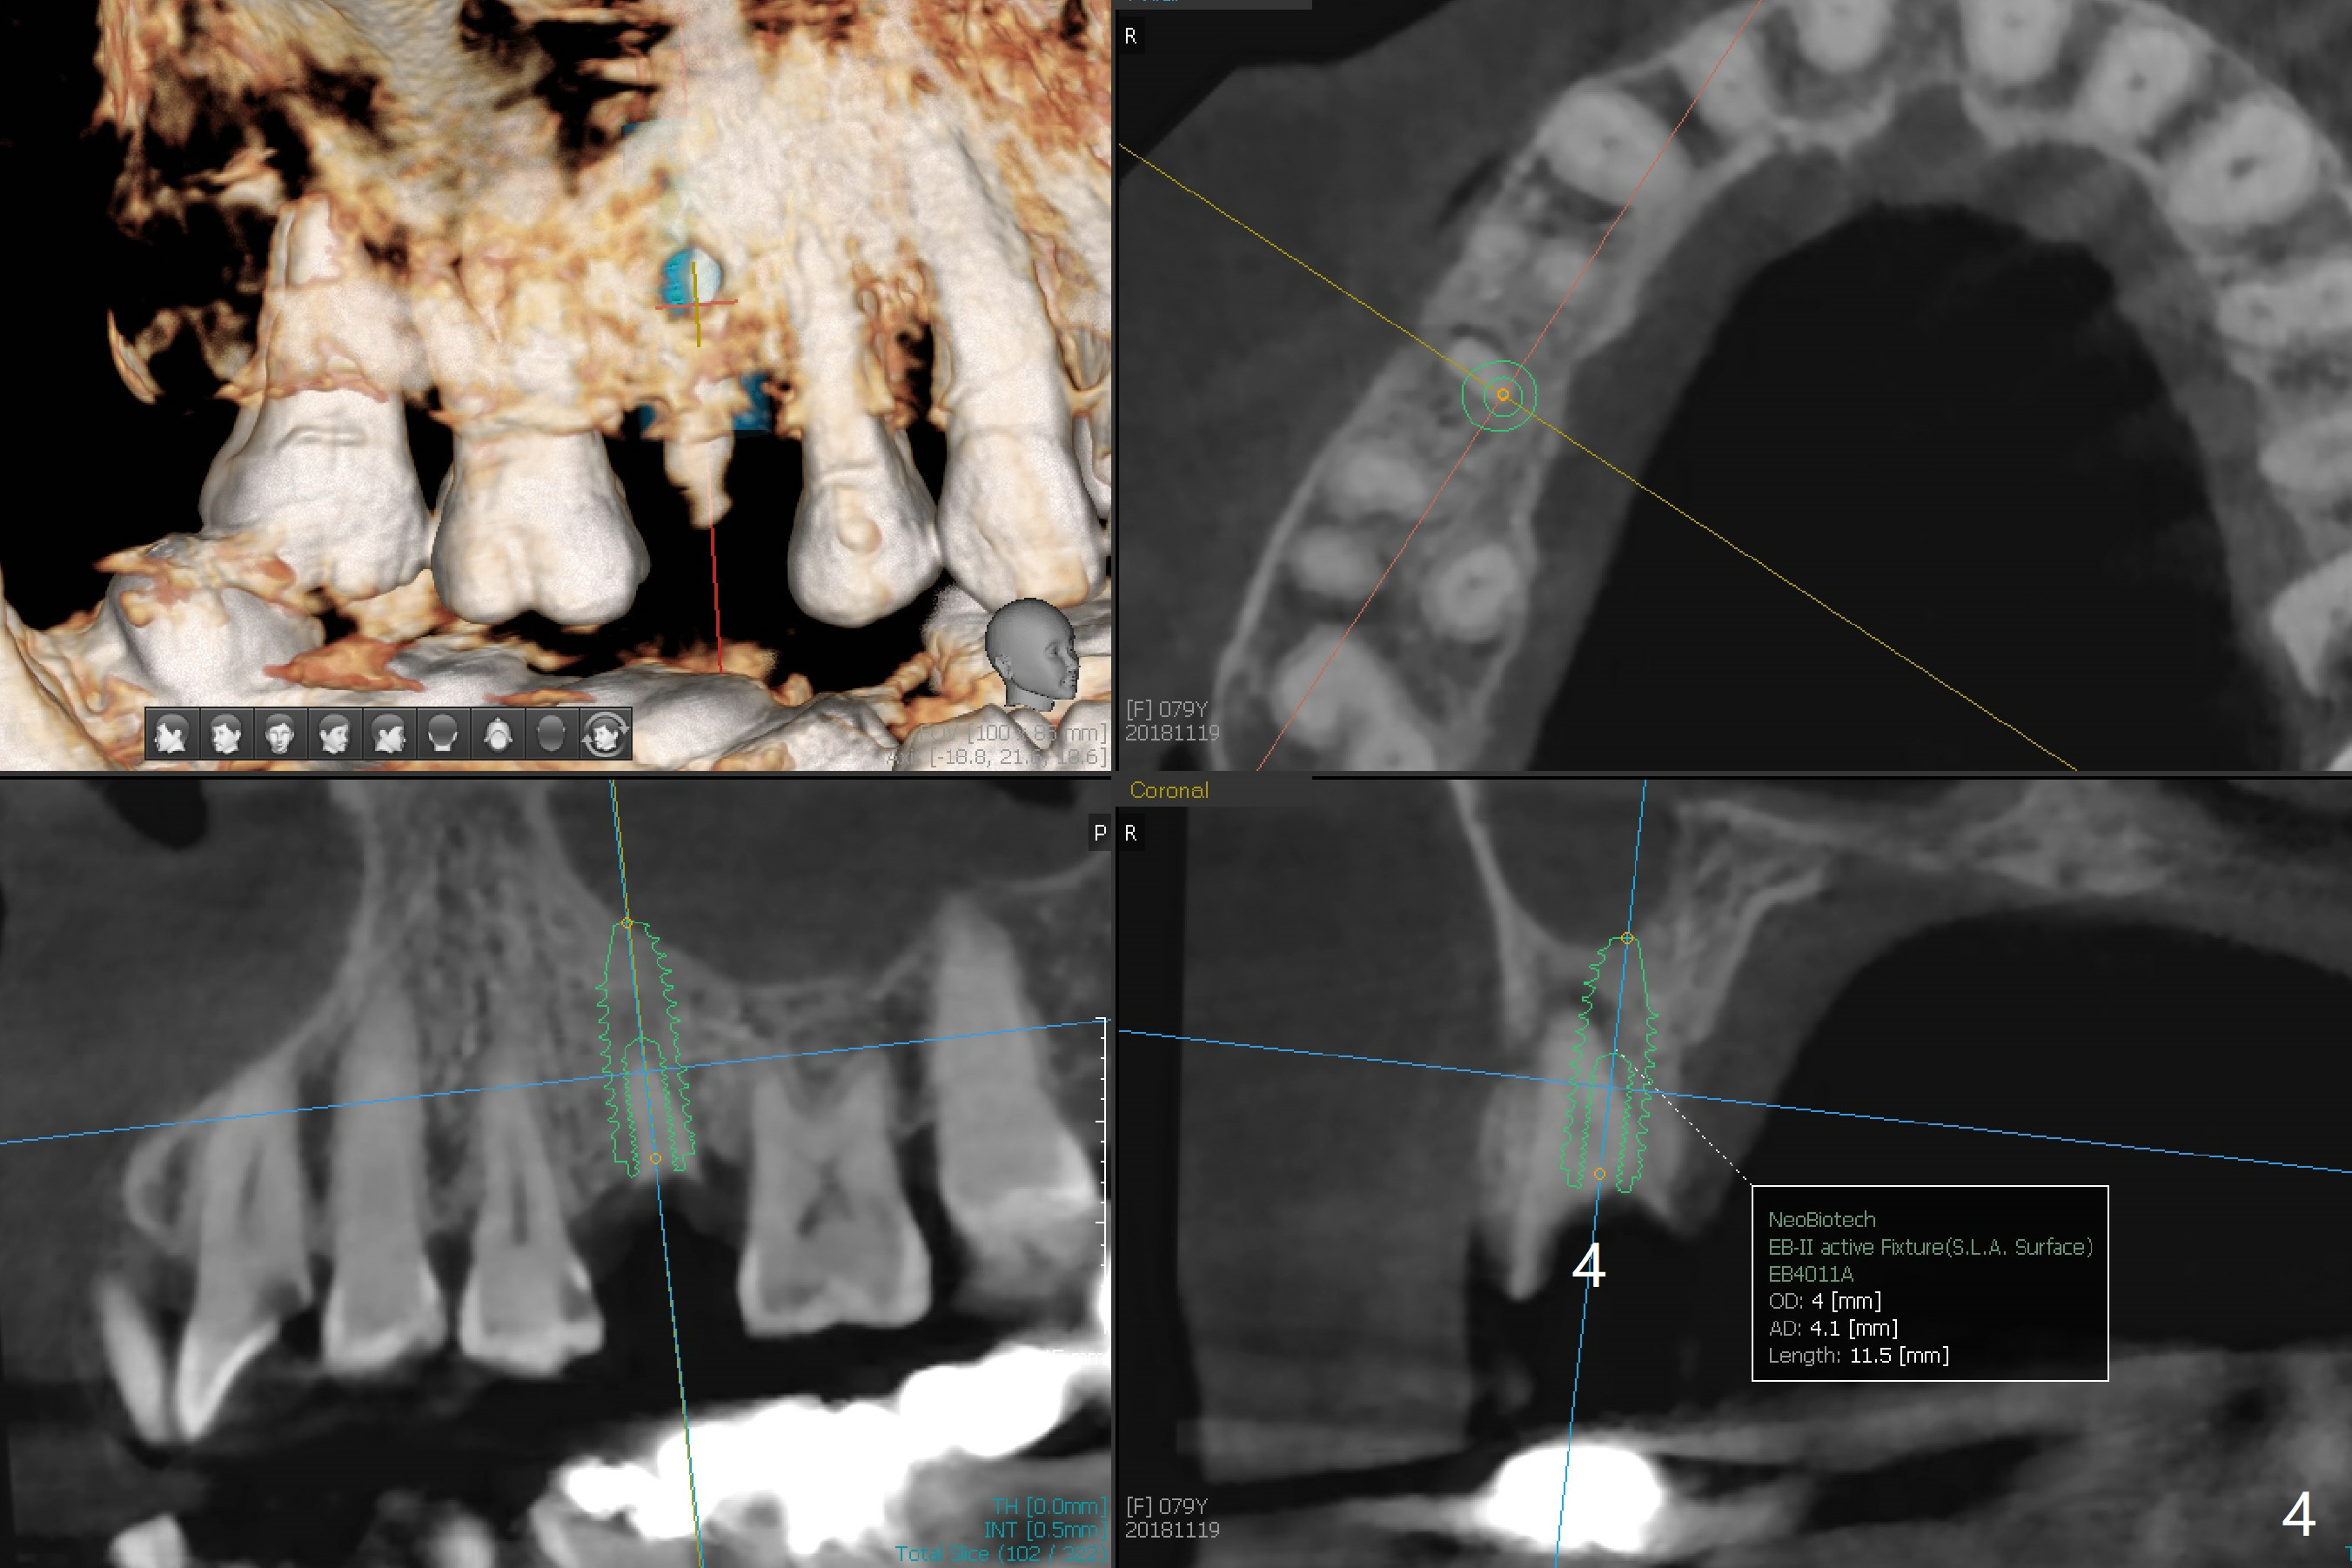

A 79-year-old woman has subgingival symptomatic caries at #14 and residual roots at #4 and 21 (Fig.1). Because of bilateral thick sinus membrane (Fig.2 *) with nasal obstruction, immediate implants at #14 and 4 will be placed without sinus lift (Fig.3,4). To obtain primary stability, a long implant will be placed at #21 (15 or 16 mm), while a narrower implant (3 mm 1-piece, Fig.6)) is safer than 3.8 mm one (2-piece, Fig.5) in term of preventing periimplantitis (buccal thread exposure). Impression has been taken for guide at #14.